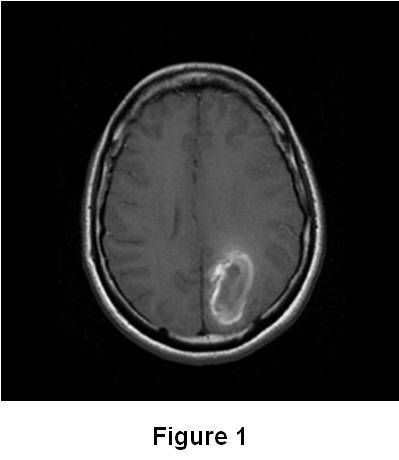

Dural venous thrombosis icd 10

- Cerebral dural venous sinus thrombosis icd 10